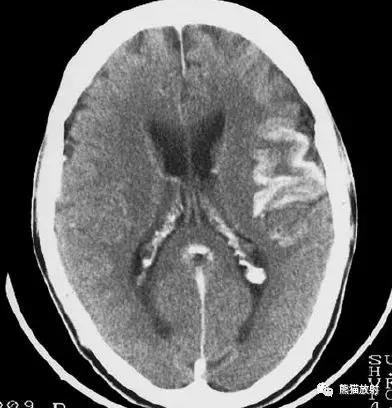

大脑中动脉区梗死:部分梗死,仅累及左侧浅表区域。

左侧大脑中动脉区完全梗死,对邻近的侧脑室产生占位效应;右侧可见其他较小的缺血性低密度区。

右侧大脑前动脉供血区部分梗死

右侧大脑后动脉供血区梗死